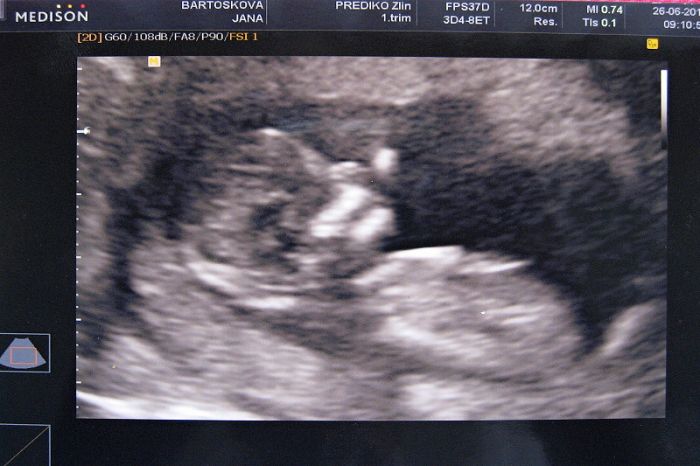

Ahojky. Dneska jsem taky byla na screeninu a mám už i výsledky. Riziko mám 1:30000. takže super. Jsem moc ráda. Byl semnou i tatínek a myslím si, jak to popisoval doma, že je z toho nadšený. Miminčo má necelých 7cm a bylo vidět vše od hlavy až k patě. Krásné. Slyšeli jsme i srdíčko. Taky se nás doktor ptal jestli chceme vědět pohlaví - tak prý na 60% kluk. Ale nějak se na to nefixuju. Pořád věřím v holčičku. Máme totiž v rodině samé kluky. Tak bych ráda to prokletí už zrušila.